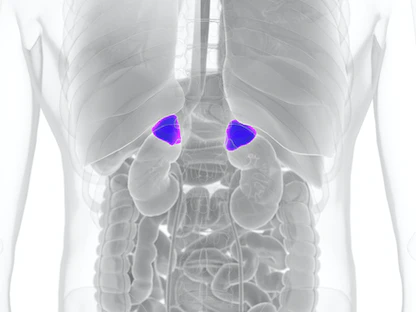

أورام الغدد الكظرية

ينشأ ذلك النوع من الأورام في الغدد الكظرية، وهي غدد صغيرة تقع فوق الكليتين، وتنتج هرمونات حيوية مثل الألدوستيرون، والكورتيزول، والهرمونات الجنسية.

وبسبب موقعها ووظيفتها، تُعتبر تلك الأورام أحد الأسباب الرئيسية للإصابة بـ"فرط الألدوستيرونية الأولية"، وهي حالة تؤدي إلى إفراز كميات زائدة من الألدوستيرون، مما يسبب ارتفاع ضغط الدم.